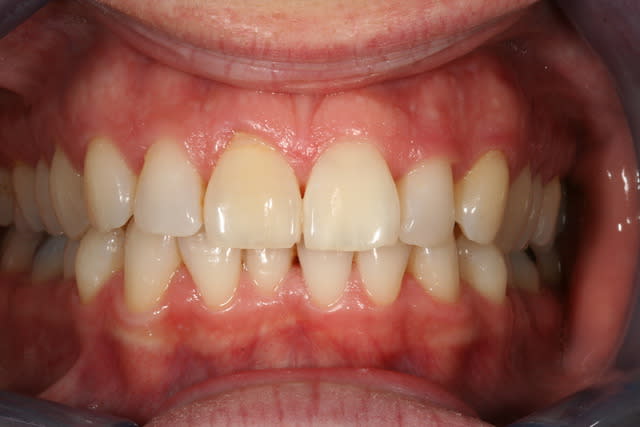

Cas simple et pourtant ... j'ai été obligé de prendre un risque . Lequel ?

C'est un blanchiment unitaire sur dent vivante ayant eu traumatisme.

C'est un blanchiment interne comme si l'endo était faite (après recherche effrénée d'un hypothétique canal), et après contrôle +++ d'une isolation +++ . La patiente n'a aucun souvenir d'un traumatisme sur cette dent .

3 séances à 7 jours d'intervalles .

Si on décide d'être le moins invasif , j'ai jugé raisonnable de tenter quand même malgré l'impossibilité de repérage de l'entrée du canal . Faire une facette c'est passer un cap , et je n'ai de prothésiste capable de reproduire les stries visibles sur la photo de départ de tout façon donc je n'ai compté que sur moi même .